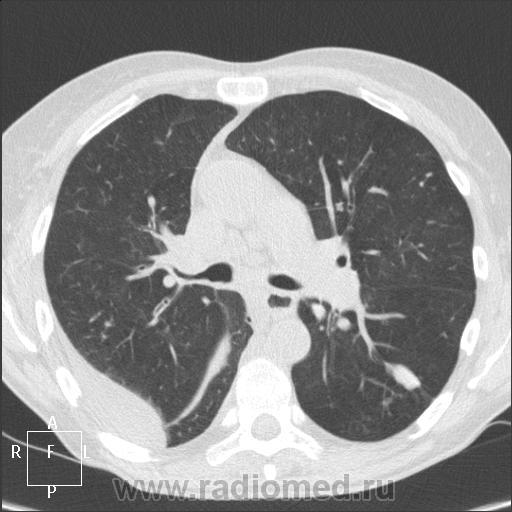

КТ легких. Как думаете, в каком отделении должна находиться пациентка?

Женщине 49 лет, 3 недели находилась в ЦРБ другого района. Переведена к нам, мол, разбирайтесь)). Диагноз при переводе: правосторонняя пневмония, цирроз печени, полиорганная недостаточность. Пьющая.

Только поступила. Клиника вроде за пневмонию, фебрильная температура, кашель с трудно отделяемой мокротой, слабость, желтуха... В выписке анемия, СОЭ 25-45, палочкоядерный сдвиг. Креатинин повышен. Лечили антибиотиками внутривенно и внутримышечно, а через 3 недели с той же клиникой перевели в нашу ЦБР. Направлена на КТ легких с напутствием констатировать исход пневмонии в пневмосклероз.

В верхней доле и в С6 слева-туберкулемы?Кроме того, в верхней доле левого легкого парасептальная эмфизема и фиброзные изменения.

Какой-то деструктивный процесс в толще массивной, по-видимому, воспалительной инфильтрации в нижней доле правого лёгкого. Справа же частично осумкованный паракостально-парамедиастинальный (а может и междолевой) плевральный выпот. Слева в верхней доле и нижней доле по фокусу неправильной формы, имеют связь с плеврой и корень нехорош. Для начала можно в торакальное отд. поместить. Анализы доделать... А там, глядишь, и в ПАО созреет, Пьющая женщина.

Мне случай показался интересным, я еще не видела столько туберкулом. И думаю на правостороннюю деструктивную пневмонию, вроде и секвестр имеется. Вопрос в названии случая продиктован выраженным нежеланием клиницистов брать пациентку. Пульмонологическое отделение боится туберкулеза и хочет видеть не туберкуломы, а метастазы... Онколог сказал: не мое. Фтизиатр считает, что данных за активный процесс нет (снимки после праздников только смогу показать - закрыты в кабинете пульмонолога).

Мое впечатление - деструктивная пневмония, секвестр. У нас торакального хирургического отделения нет. Хотелось бы еще с контрастом сделать КТ-контроль. Думаю, женщину нужно оперировать, потому что сейчас процесс отграничен на фоне массивной антибиотикотерапии, но потенциально и гангренозному абсцессу недалеко развиться. Ни на рак, ни на каверну не похоже. Хотелось бы мнение коллег узнать, какова дальшейшая диагностическая тактика в таких случаях.

Последние данные: гемоглобин 86, палочек 7, лейкоциты 11, СОЭ 78, температура 38-39.